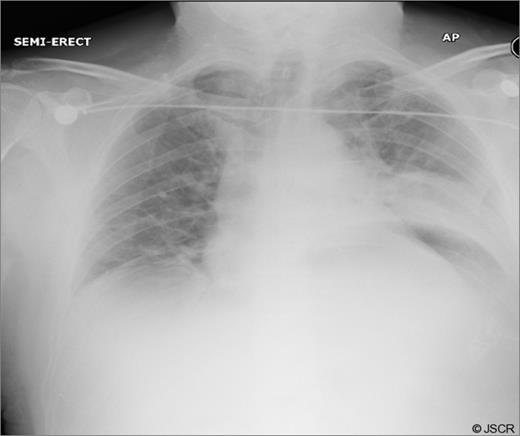

Chest pain persisted and the patient required higher pressure CPAP to maintain adequate oxygenation. Auscultation consistently showed decreased air-entry in the lung bases. On day 3, a repeat chest x-ray showed a left lower lobe collapse above the gastric bubble in the mid zone of the chest (Fig. 4 & 5). CTPA done on the same day to exclude pulmonary embolism confirmed a para-oesophageal hernia that was pushing against the left lung base. Ultrasound scan of the left chest also showed movement of the diaphragm below the gastric bubble.

Chest x-ray on 3rd post-op day showing prominent left sided collapse/ consolidation